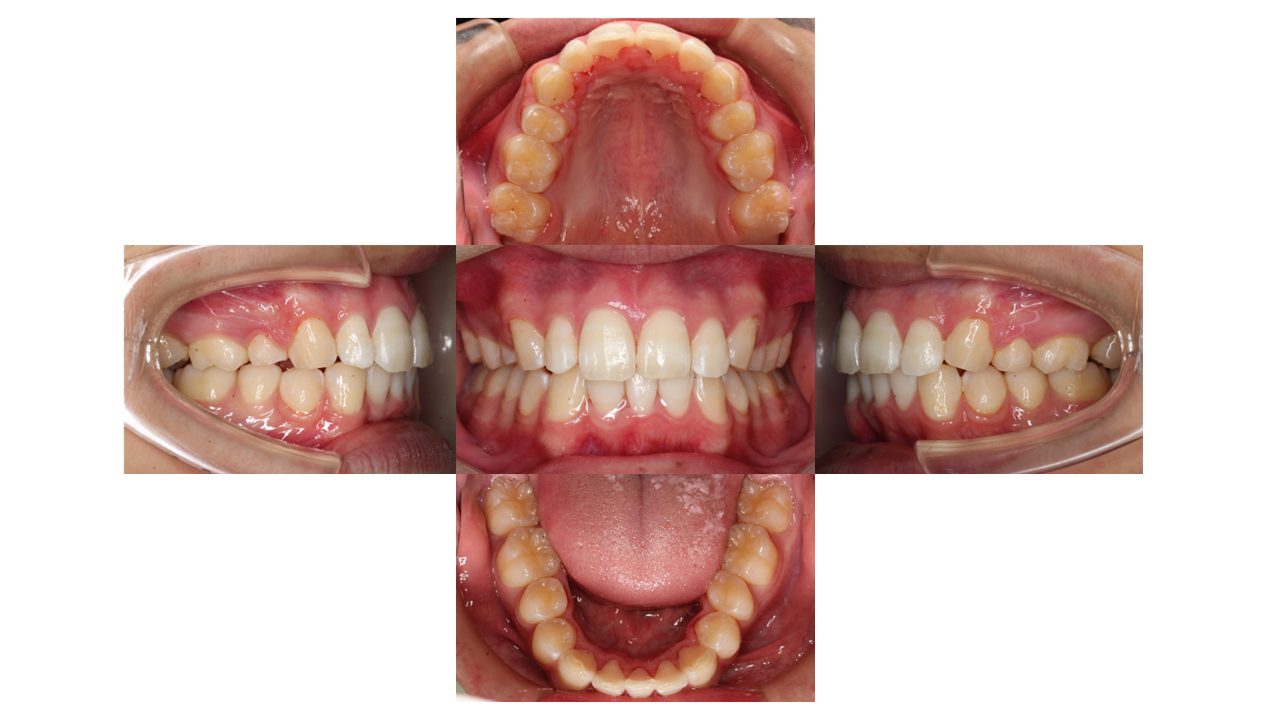

1年9カ月経過の口腔内の状態です。

上下前歯の凸凹が改善し、前歯が下がったとご満足いただけました。